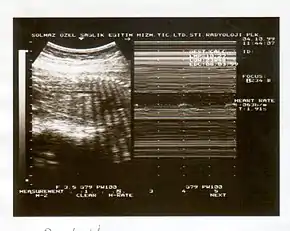

A biophysical profile (BPP) is a prenatal ultrasound evaluation of fetal well-being involving a scoring system,[1] with the score being termed Manning's score.[2] It is often done when a non-stress test (NST) is non reactive, or for other obstetrical indications.

The BPP has five components: four ultrasound (US) assessments and an NST. The NST evaluates fetal heart rate and response to fetal movement. The five discrete biophysical variables are:

- Fetal heart rate